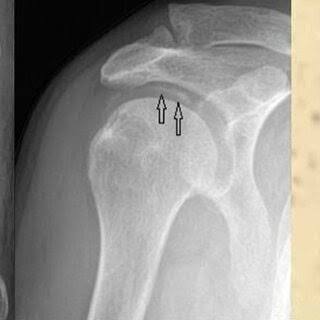

Name 2 risk factors for adhesive capsulitis

Increased risk w/ DM, thyroid disease, immobilization; age 40-60